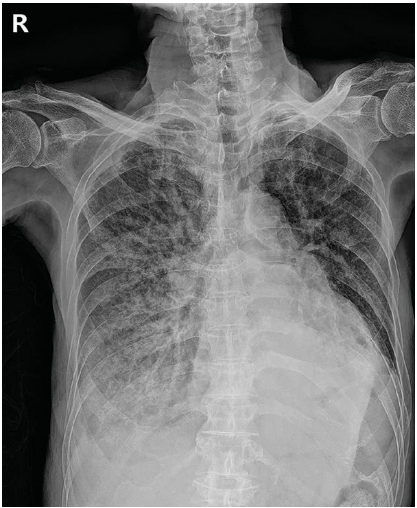

87세 남자가 3일 전부터 기침과 가래가 나온다며 병원에 왔다. 고혈압과 알레르기비염으로 치료를 받고 있다. 5일 전부터 몸살과 콧물이 있으며 식욕이 없고 누워만 있었다고 한다. 50갑·년의 과거 흡연자이다. 혈압 110/70mmHg, 맥박 84회/분, 호흡 24회/분, 체온 37.3℃이다. 의식은 명료하고, 오른쪽 가슴에서 거품소리가 들린다. 가슴 X선 사진이다. 맥박산소포화도는 84%이고 검사 결과는 다음과 같다. 조치는?

CXR: diffuse opacities, RLLF

• 신체 진찰상 발열, 빈호흡이 있고 우측 폐야 crackles가 청진되며, CXR에서 해당 부위에 opacity가 확인된다. 혈액검사상 neutrophil-dominant leukocytosis도 확인되므로 환자의 임상상을 결부하여 판단할 때 세균성 폐렴이 강하게 의심되는 상황이다.